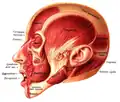

Position of buccinator muscle (red)

Position of buccinator muscle (red) -